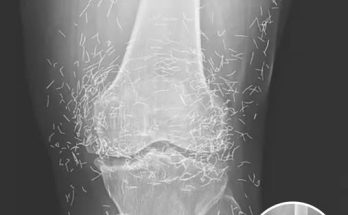

Doctors Stunned After Looking At This X-Ray Of Woman Suffering Joint Pain

A routine X-ray revealed an unexpected surprise when doctors examined the knees of a 65-year-old woman suffering from severe joint pain. What they found was nothing short of astonishing — …